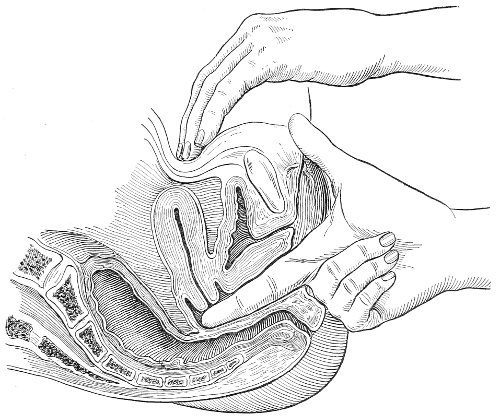

The examination of the uterus and other pelvic structures is often facilitated by dragging the uterus downward with a tenaculum while the vaginal or the bimanual examination is being made. Sensation in the cervix is so slight that little or no pain is experienced in this procedure. The anterior or posterior lip of the cervix is caught with the single or the double tenaculum (Fig. 4), guided along the vaginal finger or introduced through the speculum, and the uterus is drawn down by an assistant in case the bimanual examination is being made, or by the external hand of the examiner in case a simple vaginal examination is made. When this is done the utero-sacral ligaments are made tense, and can be felt like two cords extending from the sides of the cervix outward and backward to the pelvic wall. The posterior surface of the uterus can be palpated often as high up as the fundus. The method is especially useful when the examination is made by the rectum, and in this way the whole posterior surface and the fundus of the uterus may be palpated (Fig. 5).

Fig. 5.—Bimanual examination with one finger in the rectum. The uterus is drawn down with the double tenaculum.

Rectal examination of the pelvic structures is made in a way similar to that already described for the vaginal examination. Bimanual examination may be made by palpating the various organs between the rectal finger and the abdominal hand.